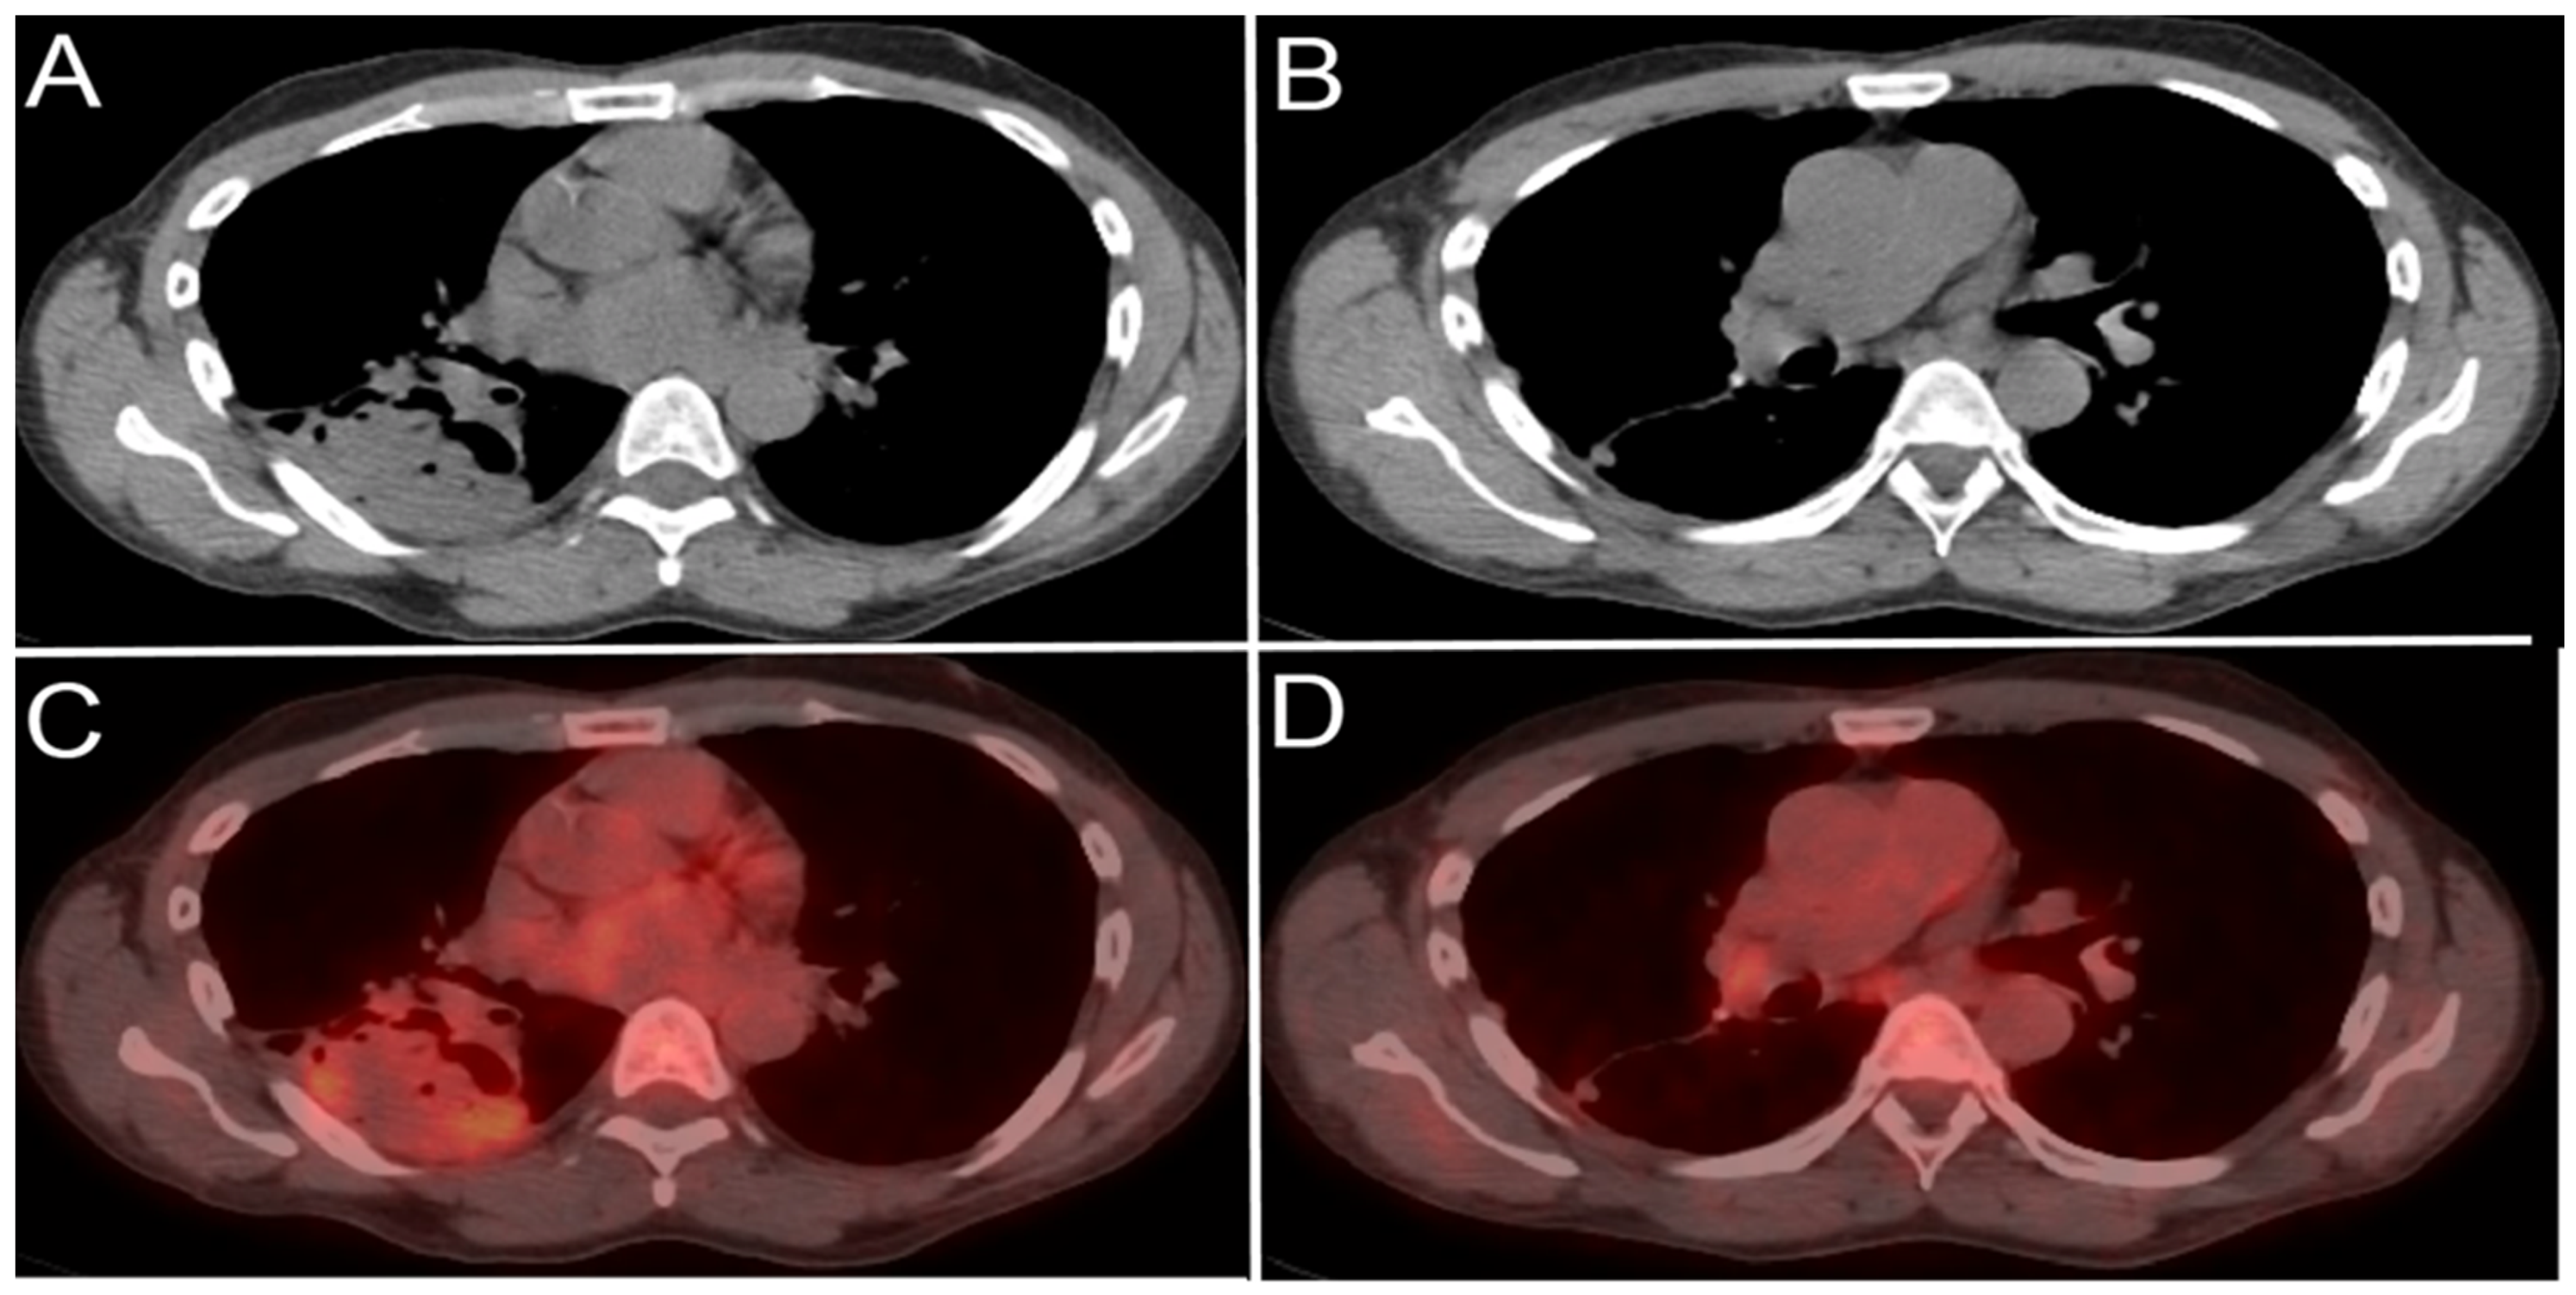

4.1.3. Positron Emission Tomography (PET) and Positron Emission Tomography-Computed Tomography (PET-CT)